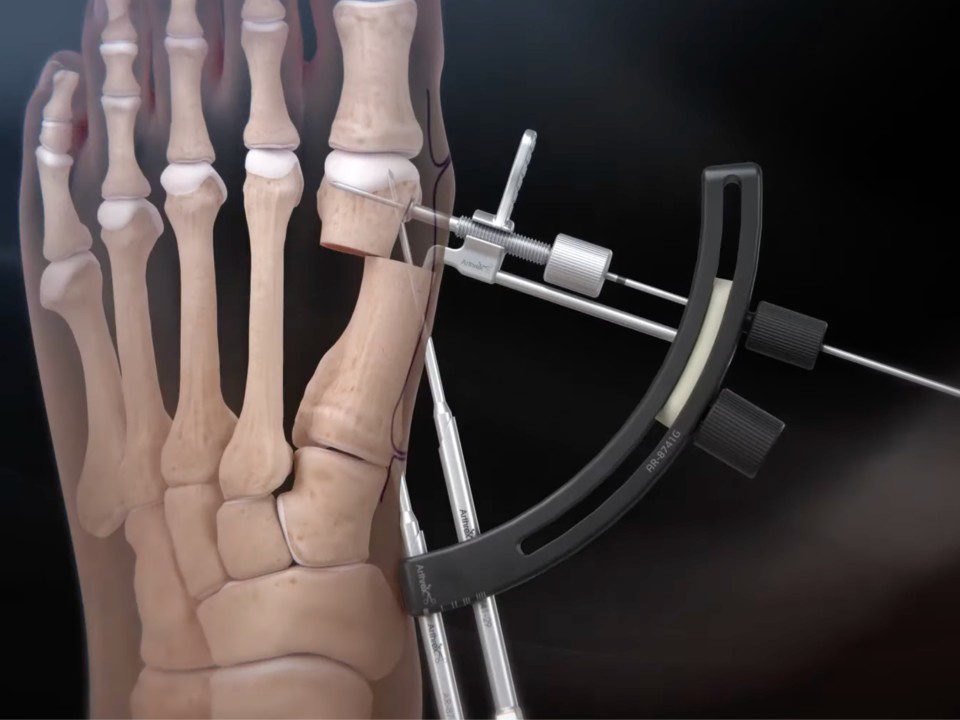

Guided Trajectory System, an innovation developed by Dr. Victor Dubois-Ferrière

Nous sommes fiers de vous annoncer la mise sur le marché mondial d’un outil de guidage pour la chirurgie mini-invasive développé par le Dr Victor Dubois-Ferrière et distribué par la société Arthrex. Ce nouvel outil nommé »Guided Trajectory System », permet aux chirurgiens d’optimiser la précision et la reproductibilité de la chirurgie percutanée ou mini-invasive de l’hallux […]